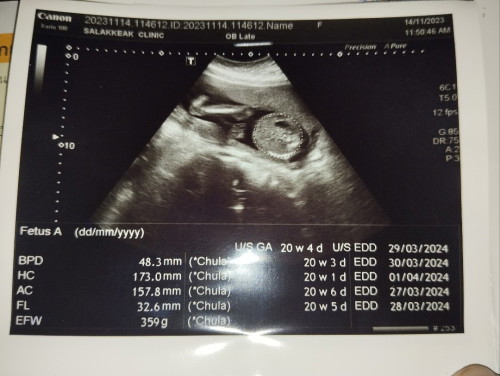

ท้องที่4แล้ว ก่อนหน้านี้แท้ง1 ท้องนอกมดลูก1 ได้ลูกสาวมา1 ตอนนี้ท้อง5เดือนได้ลูกชายสมใจ